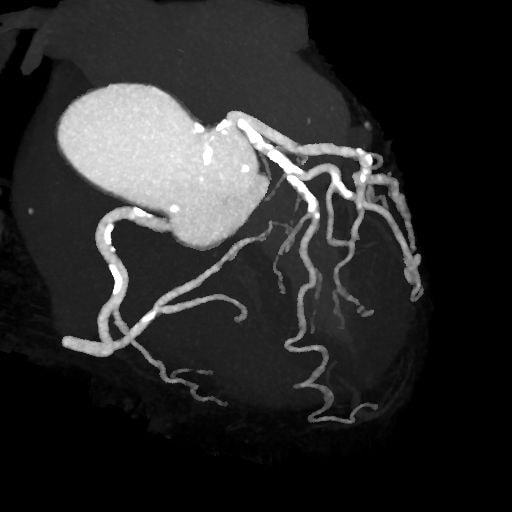

図3.アンギオグラフィックビュー

良好に造影されている。冠動脈に石灰化プラーク多数。

図4.動脈相RCA, LAD, LCX

LAD#6-7、対角枝に高度石灰化プラーク。評価困難部位あり。LCX#11非石灰化プラークあり、軽度狭窄疑い。LCX#13非石灰化プラーク、中等度狭窄疑い。